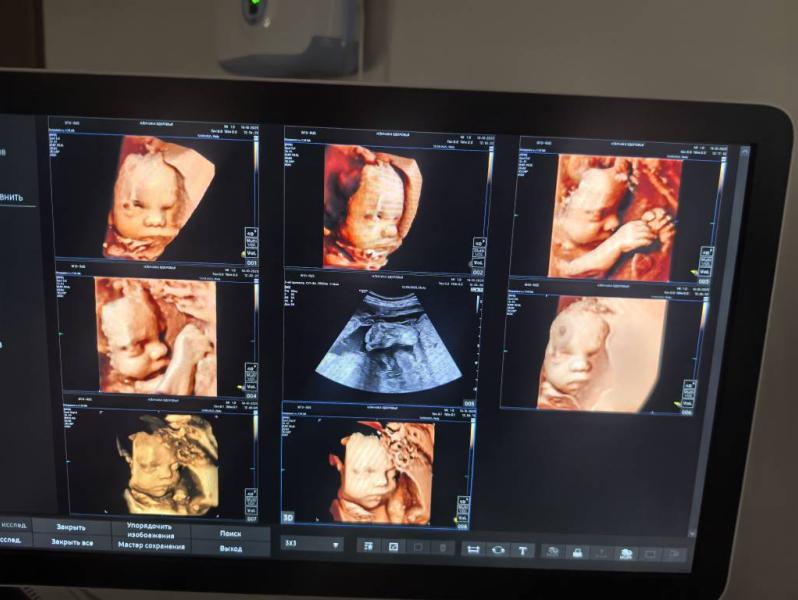

Ходили на узи

Малышка вылитый старший сын в утробе, но черты лица более аккуратные как будто видно что это девочка, милашка такая💕💕💕 в целом сказали что все хорошо все соответствует сроку только вот одно но ножки коротковаты сказали попить кальций и животик крупноват сказали поменьше есть углеводов

Про коротенькие ножки сказали уде второй раз, на предыдущем узи в сентябре тоже ножки маловаты были.... Расскажите у кого то может был опыт? Когда косточки были маловаты и животик большой 🤔